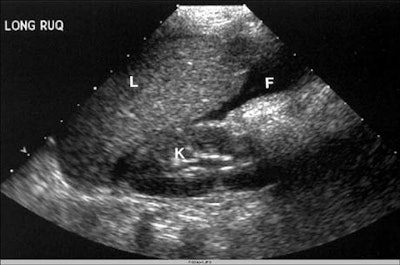

"We looked for free fluid first, and if we saw that, we looked at the parenchyma of organs. If we didn't see free fluid and if we had time, we also looked at the parenchymal organs," McGahan said. The ultrasound was then followed up with either CT or laparotomy, he said.

Ultrasound detected organ injuries in 9 patients (12%) in which no free fluid was identified. These included 3 splenic injuries, 3 liver injuries, and 3 renal injuries, for an approximate sensitivity of 70%, McGahan said. The inclusion of sonographic identification of parenchymal organ injury increased the sensitivity of ultrasound to 86%, with overall accuracy of 96%.

"In conclusion, emergency ultrasound is highly accurate and specific, but has moderate sensitivity for the detection of free fluid in pediatric abdominal blunt trauma patients. Some of our identification of actual organ injury was in the form of parenchymal abnormalities -- when you do identify [them], it does improve the sensitivity of ultrasound," he said.